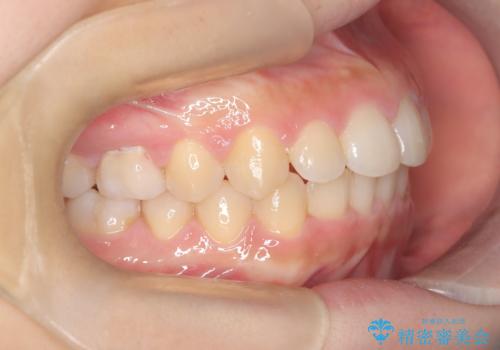

【ワイヤー矯正】前歯のがたがたをなおしたい

- 前歯のがたがたを主訴に来院されました。

叢生量も軽度なため短期間で治療を行っています。

治療中、装置の変更を希望されたため上下で装置が異なっています。